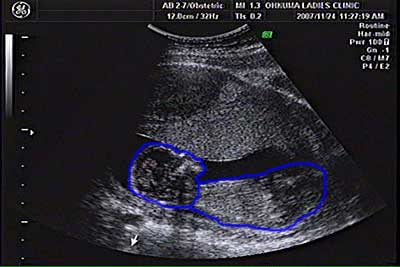

| 胎児のエコー写真 2007/11/24 |

| 左が頭部,右が腹部 |